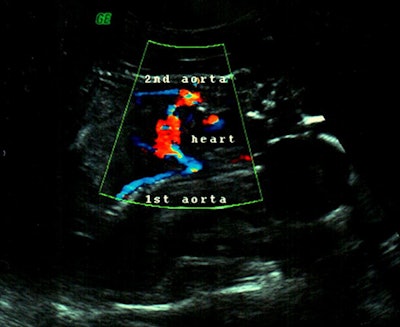

A Voluson 730 ultrasound machine from GE Healthcare (Waukesha, WI) was used. The transabdominal ultrasound was performed, and two conjoined female fetuses were detected; each fetus was with a single head and a pair of arms and legs. The twins were joined at the lower chest and the upper abdomen. Only one functional fetal heart was observed centrally between both the fetuses with slight tendency toward one of the fetuses (figures 1 and 2). Single anterior placenta was seen with the umbilical cord and a normal amount of fluid. The color Doppler study showed two aortic arches emerging from the single functional heart (figure 2). On the basis of these findings, a diagnosis of dicephalic thoraco-omphalopagus conjoined twins was made (figure 3).